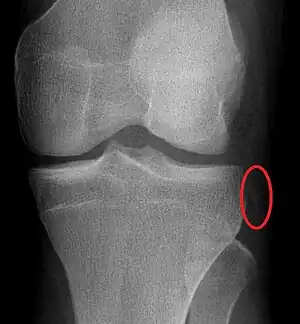

| Segond fracture | Paul Segond | lateral tibial plateau avulsion fracture with anterior cruciate ligament tear | Segond fracture at Who Named It? | ![]() | |